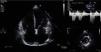

The setting was interpreted as acute HF, and etiological investigation included electrocardiography (ECG) and transthoracic echocardiography (TTE). The ECG showed atrial fibrillation (AF) and a mean ventricular rate of 130 bpm, but no ST-T segment abnormalities (Figure 3).

TTE, performed with the patient in AF, showed degenerative changes in valve structures with no significant hemodynamic compromise and mild to moderate tricuspid regurgitation, with pulmonary artery systolic pressure (PASP) estimated at 36 mmHg and right atrial pressure at 20 mmHg. There was mild right chamber dilatation (right atrial area 26cm2), with flattening of the interventricular septum secondary to right ventricular (RV) overload (Figure 4), RV systolic function at the lower normal limit (tricuspid annular plane systolic excursion 1.7cm; S wave 13cm/s) and mild inferior vena caval dilatation (28mm) with reduced respiratory variation, all compatible with pulmonary hypertension (PH). There was also moderate left atrial dilatation (area 31cm2), with normal left ventricular (LV) dimensions (end-diastolic diameter 52mm) and ventricular wall thickness. LV systolic function (LVSF) was mildly impaired, with a mean ejection fraction of 46% and increased LV filling pressures (septal E/E′ 21.9).